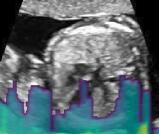

Sound-opaque occluders, including bones and calcified tissues, block the propagation of sound waves by strongly absorbing or reflecting sound waves during scanning. The regions behind these sound-opaque occluders return little to no reflections to the US transducer. Thus these areas have low intensity but very high acoustic impedance gradients at their boundaries (e.g. Fig. 1(a) left column). Reducing acoustic shadows and correct interpretation of images containing shadows rely heavily on sonographer experience. Experienced sonographers avoid shadows by moving the probe to a more preferable viewing direction during scanning or, if no shadow-free viewing direction can be found, a mental map is compounded with iterative acquisitions from different orientations.

We propose a novel method based on convolutional neural networks (CNNs) to automatically estimate pixel-wise confidence maps of acoustic shadows in 2D US images. Our method learns an initial latent space of shadow regions from images consisting of multiple anatomies and with global image-level labels (“has shadow” and “shadow-free”), e.g. Fig. 1(a). The basic latent space is then estimated by learning from fewer images of a single anatomy (fetal brain) with coarse pixel-wise shadow annotations (approximately of the images with global image-level labels), e.g. Fig. 1(b). The resulting latent space is then refined by learning shadow intensity distributions using fetal brain images so that the latent space is suitable for confidence estimation of shadow regions. By using shadow intensity information, our method can detect more shadow regions than the coarse manual segmentation, especially relatively weak shadow regions.